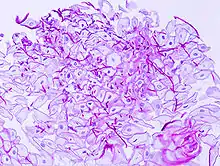

A severe case of esophageal candidiasis

In most cases, the diagnosis is established based on response to therapy. Patients in whom esophageal candidiasis is suspected should receive a brief course of antifungal therapy with fluconazole. If the infection resolves after treatment with fluconazole, then the diagnosis of esophageal candidiasis is made and no further investigation is needed. However, if the infection persists or if there are other factors involved which may warrant further investigation, then patient will undergo an esophagogastroduodenoscopy if it is safe to do so. Endoscopy often reveals classic diffuse raised plaques that characteristically can be removed from the mucosa by the endoscope. Brushing or biopsy of the plaques shows yeast and pseudohyphae by histology that are characteristic of Candida species.